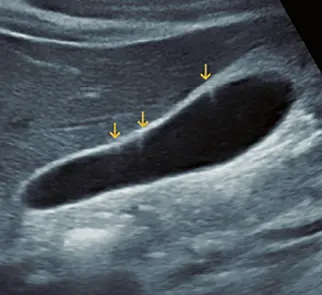

Fig: 9–a

Fig: 9–a, Se observa una formación mixta: sólida (flecha gruesa) y quística (indicadores, existen tabiques con grosor variables, algunos mayores de 3. 0 mm (flecha).

Fig: 9–b

Fig: 9–b, pieza quirúrgica la cual corresponde un Ca renal mixto: sólido–quístico.